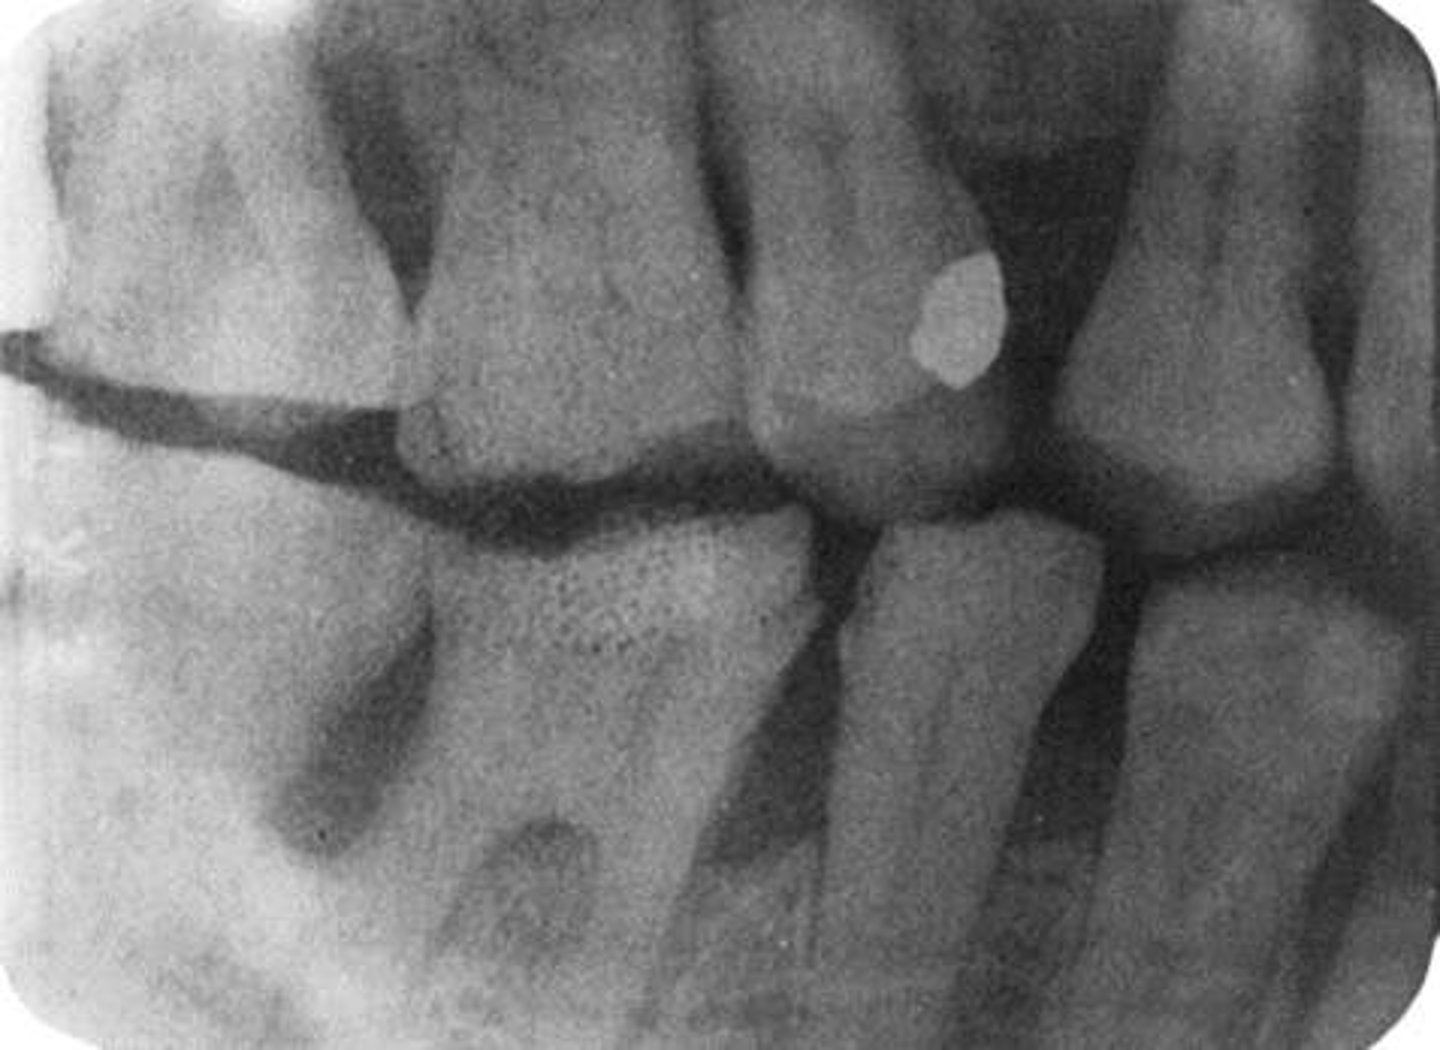

Cone-Cut with Beam Alignment Device

-A clear unexposed area is seen

-PID was not properly aligned with the PA beam alignment device and the beam did not expose the entire receptor, resulting in a clear unexposed area resembling the outline of the PID is seen

-To avoid make certain that the PID and the aiming ring are aligned

Cone-Cut without Beam Alignment Device

-PID was not directed at the center of the receptor, resulting in a clear unexposed area resembling the outline of the PID

-To avoid position the PID and the x-ray beam centered over the receptor and that the entire receptor is covered by the diameter of the PID

Tube Head & PID-->Cone-cut Error

Cause - Primary beam not directed toward the center of the image receptor or image receptor not lined up correctly to the PID

-Occurs more commonly without using XCP or external aiming device